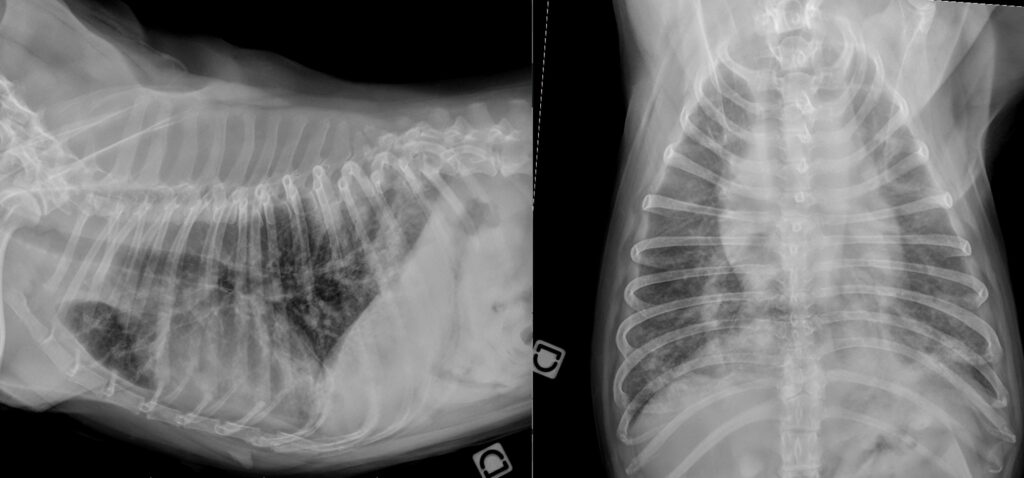

Quelles sont les opacités anormales visibles sur ces radiographies (profil latéral droit et VD) ?

1 – Opacité bronchique.

2 – Opacité interstitielle et bronchique.

3 – Opacité bronchique et alvéolaire.

Si vous avez coché le choix 3, c’est la bonne réponse 😁

Sur ces radiographies on note opacification alvéolaire caudodorsale multifocale et bilatérale, à l’origine d’une perte complète de la visualisation des vaisseaux superposés. On note aussi une opacification bronchique généralisée avec augmentation de l’épaisseur visible des bronches en coupe transverse et longitudinale pouvant représenter un épaississement vrai des parois bronchiques ou un épaississement des tissus péribronchiques (vasculaires et lymphatiques notamment).

La combinaison de ces deux opacités associées à cette distribution particulière, caudodorsale, permet de favoriser une hypothèse parasitaire (Angiostrongylose) en priorité dans notre diagnostic différentiel. Les autres hypothèses considérées de manière moins probable seront les coagulopathies, les thromboembolies et les infections pulmonaires hématogènes.